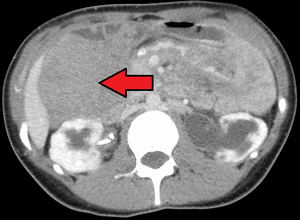

DesmoidTumorCTCorMark.png

ورم رباطي كما هو موضح في الاشعة المقطعية